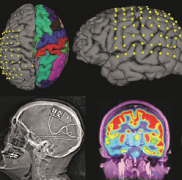

癲癇能治好嗎?INC加拿大Rutka教授解讀癲癇手術(shù)進(jìn)展和臨床成功案例

癲癇能治好嗎?作為國際小兒腦瘤/癲癇治療專家,INC旗下國際神經(jīng)外科顧問團(tuán)(WANG)專家成員、國際神經(jīng)外科學(xué)院前主席James T. Rutka教授在2016 CNS Annual Meeting上發(fā)表了主題為《癲...